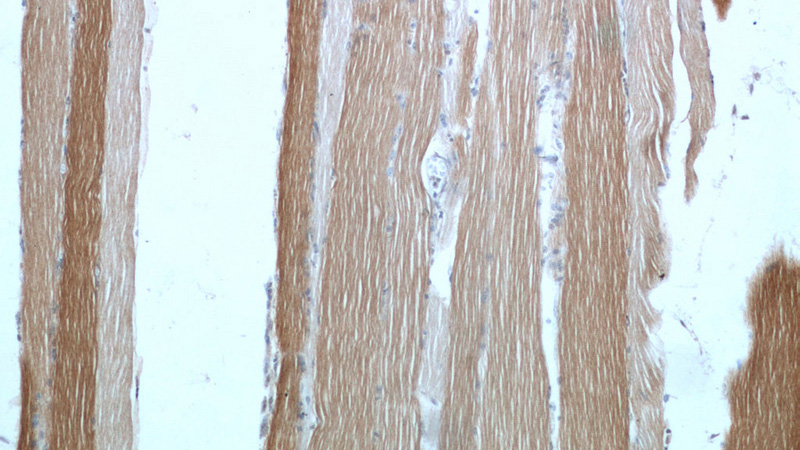

Immunohistochemical of paraffin-embedded human skeletal muscle using Catalog No:116151(TNNI1 antibody) at dilution of 1:50 (under 10x lens)